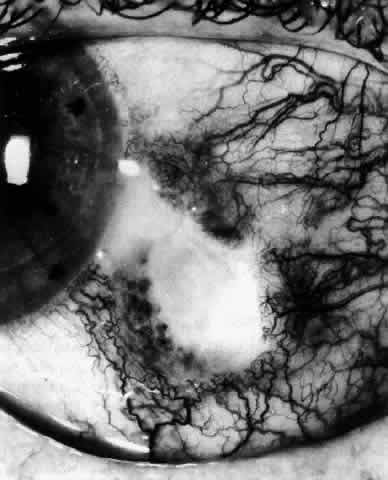

The characteristic features of necrotizing scleritis on fluorescein angiography are hypoperfusion and, eventually, nonperfusion of the vascular networks (Figs. 40 through 43).26 The initial changes are on the venous side of the capillary network; the transit time of the dye increases even if the eye is red and congested. If the disease process persists or has been present for a long time, thrombosis and permanent vaso-occlusive changes occur. These vessels (or the occluded capillary network) are bypassed by the opening of anastomotic channels. New vessels in a granuloma give rise to deep intrascleral leakage of dye (see Fig. 43). Conjunctival and episcleral involvement by the destructive change is late but is always preceded by vaso-occlusive changes that can sometimes be detected with use of the red-free light on the slit lamp (Figs. 44 and 45).

Fig. 40. Early necrotizing scleritis. There is characteristic yellow discoloration of the sclera underlying the conjunctiva at a point of necrosis. In this instance a small filament of tissue has penetrated the conjunctiva.

Fig. 41. Late stage of fluorescein angiogram adjacent to the site of necrosis in the same patient as in Figure 40. Although the eye is uniformly congested, the area near the necrosis shows vascular shutdown, whereas the rest of the conjunctiva and episclera is normally perfused.

Fig. 42. Late arterial phase of fluorescein angiogram in a patient with necrotizing scleritis. All the vessels except the main trunk and the vessels around the limbal perforating vessels are occluded and remain unperfused throughout the angiogram.

Fig. 43. Late venous phase of angiogram of a patient with necrotizing scleritis showing late deep leakage from vessels on the surface of the sclera and leakage of the capillary network at the limbus and the vessels draining it, together with poor or absent perfusion of the remaining vessels.